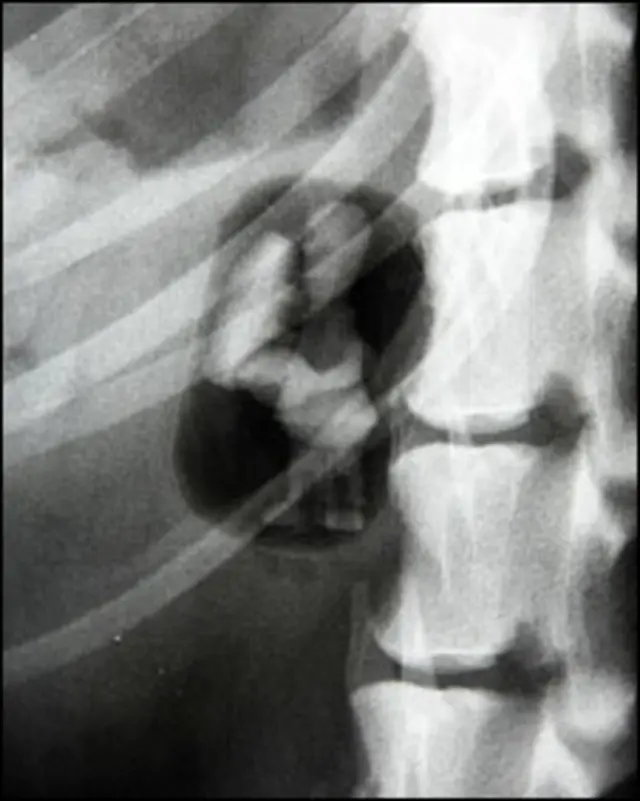

Os veterinários suspeitavam que havia um corpo estranho dentro de Dixie e isto foi confirmado com exames que mostraram um objeto estranho que acabou sendo retirado do intestino.

"Os (exames de) raio X confirmaram que havia um corpo estranho, mas foi uma grande surpresa ao descobrirmos um ovo plástico com o Homer Simpson dentro. Vemos muitos objetos que foram engolidos por animais, mas este foi um dos mais diferentes", acrescentou a cirurgiã.